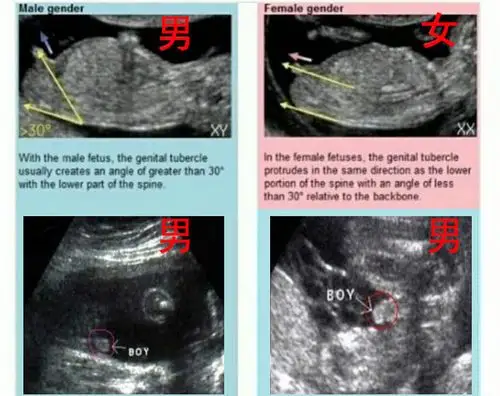

怀孕十二周,生男生女这样看._手机搜狐网